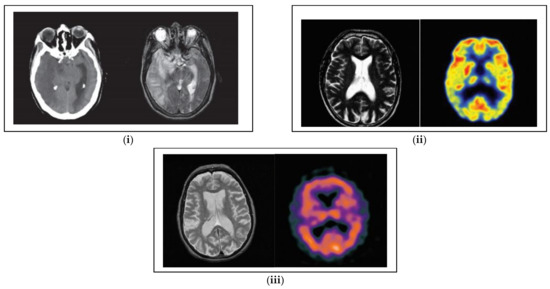

The proposed approach is verified effectively using 270 pairs of source images. The entire sample of source images was gathered from the Whole Brain Atlas of Harvard Medical School. The examinations were conducted using a set of images that contains CT, MRI, SPECT, MRI, and PET images. The database images are depicted in Figure 3. All the source images contain an identical spatial resolution of 512 × 512 pixels by 256 gray scale levels. The proposed HOD-CNN is computed in MATLAB 2018a with the system requirements being a i7 processor and 8 GB RAM. For the investigation purposes, the database was classified into 75:25 for testing as well as training purposes. Table 2 describes the parameters of the proposed algorithm.

Figure 3. Database image (i) CT and MRI, (ii) MRI and PET, and (iii) MRI and SPECT.